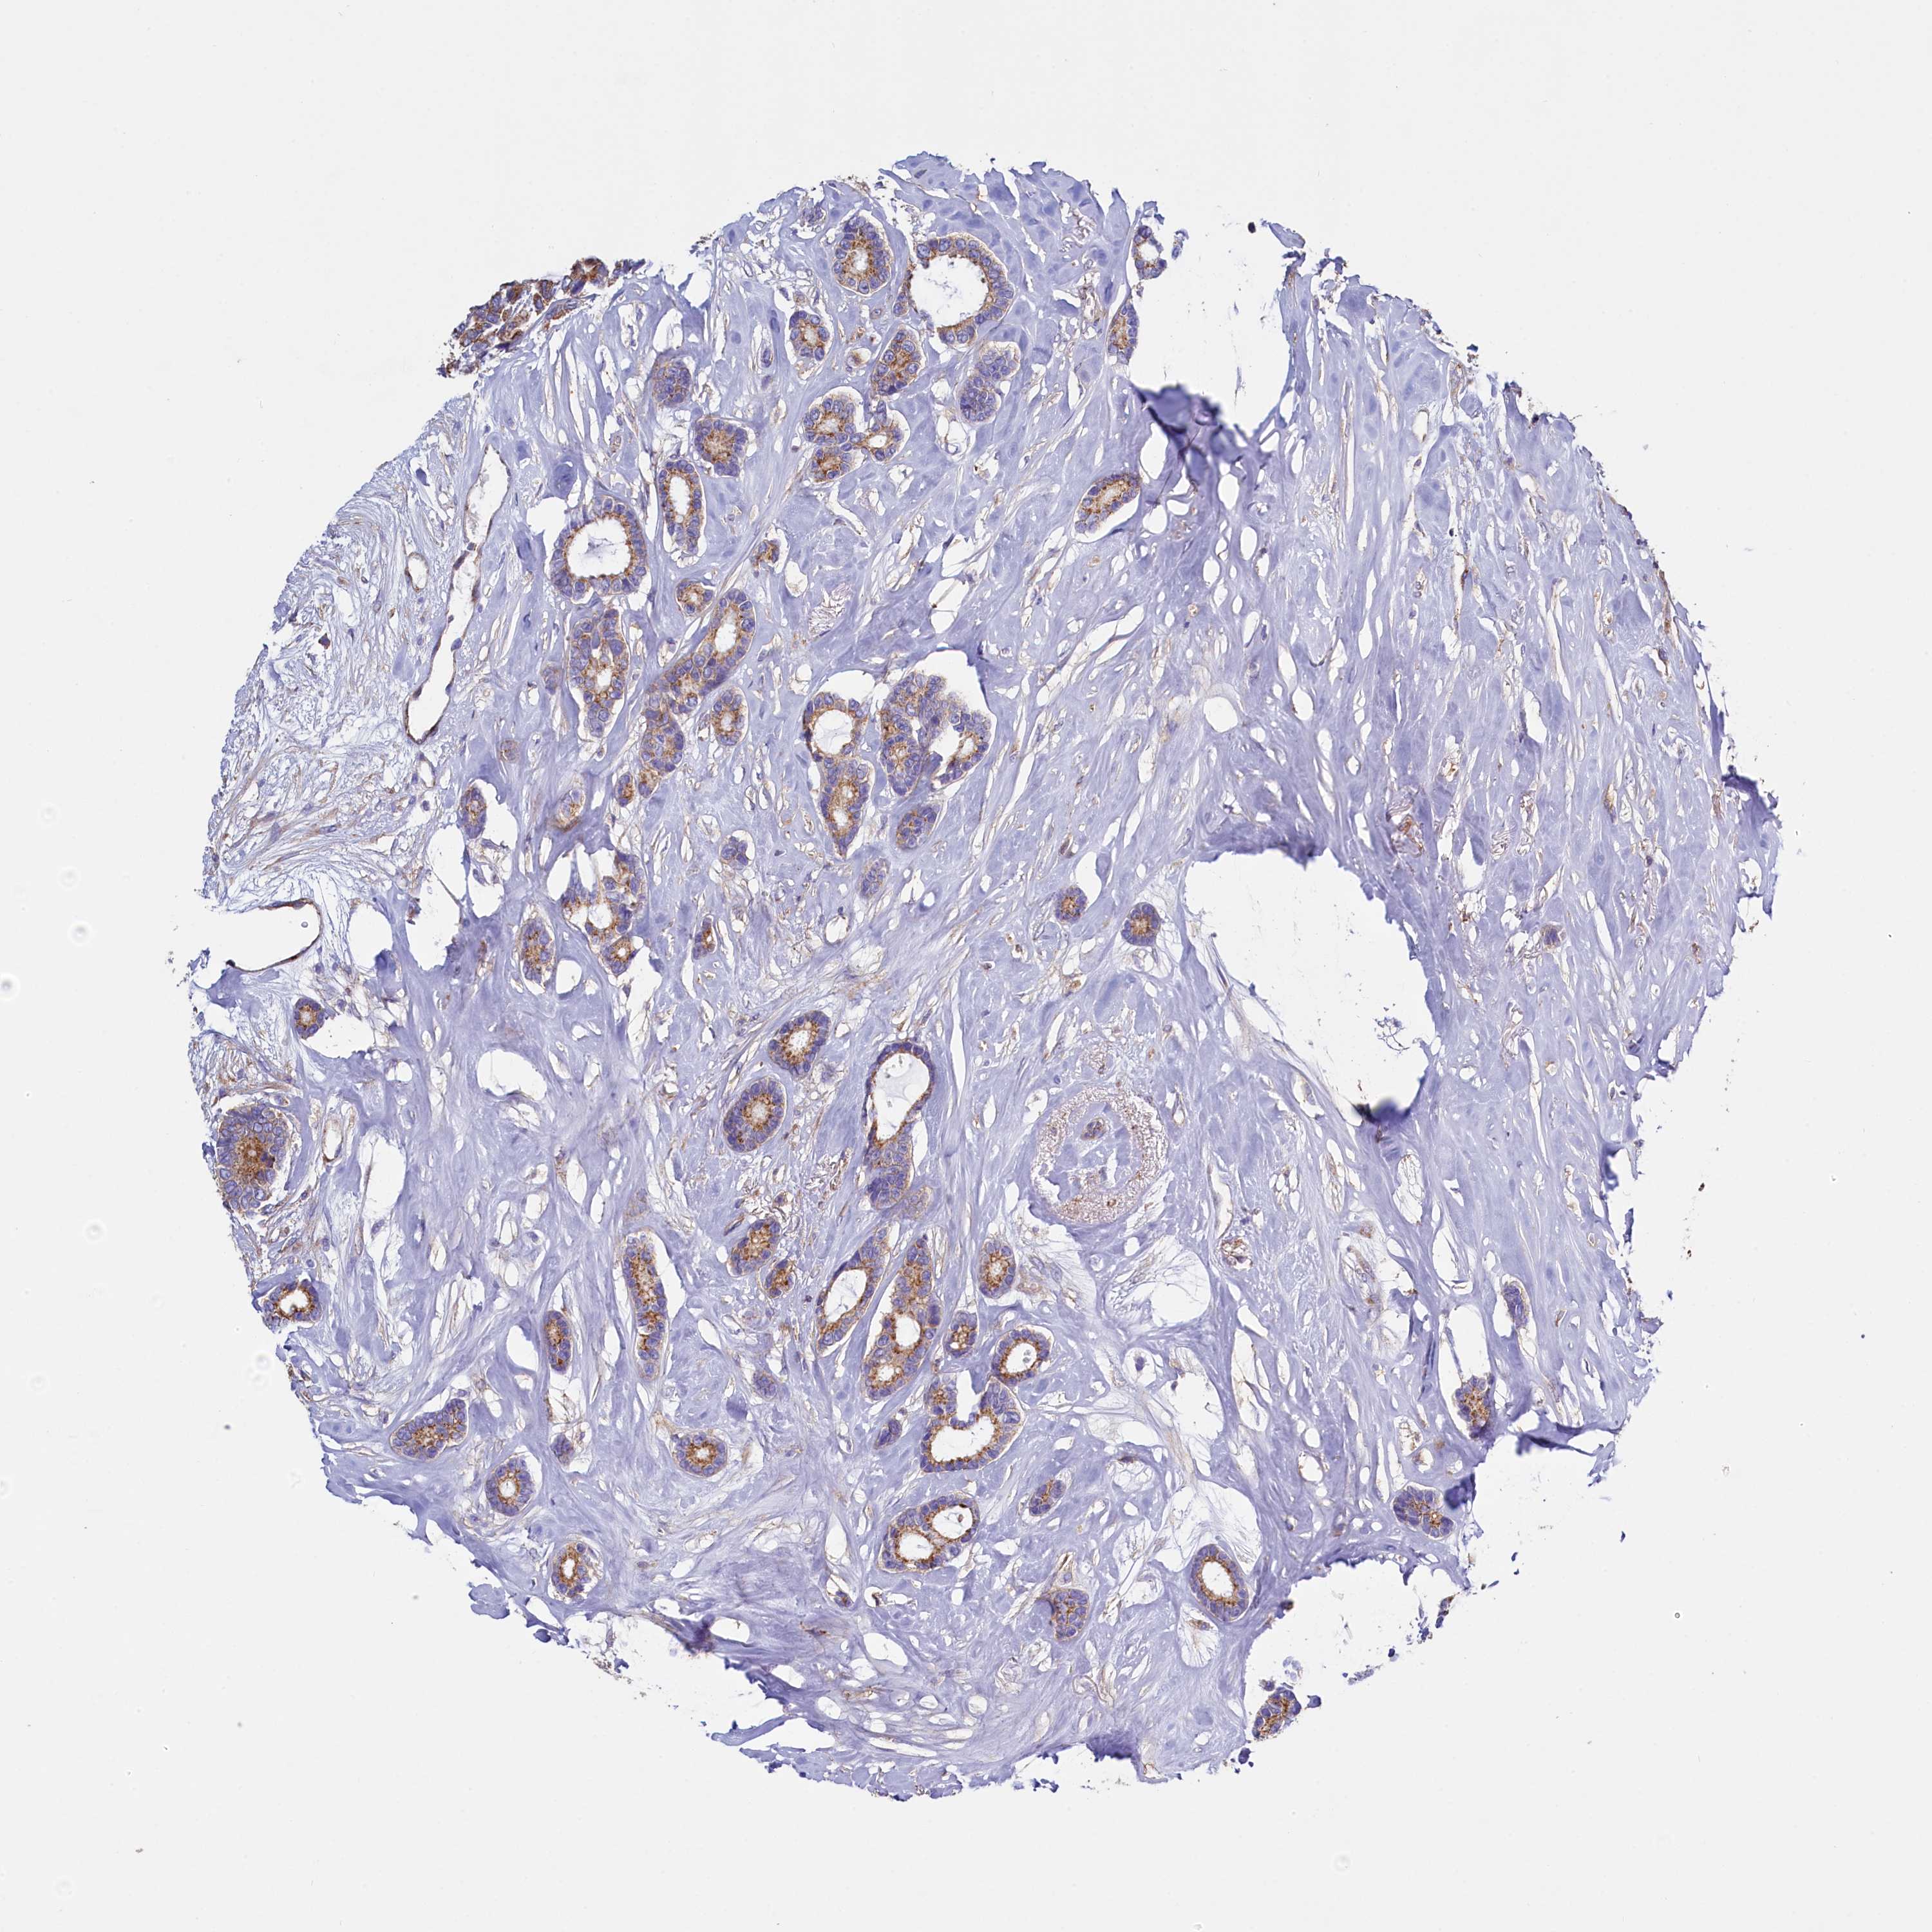

CANCER BREAST CANCER Show tissue menu

BRCA TCGA BRCA VALIDATION PROTEIN EXPRESSION